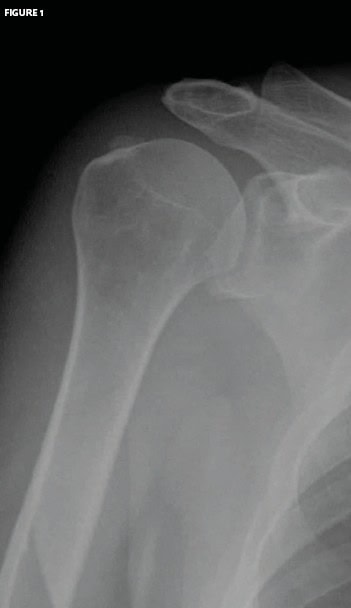

The patient is a 62-year-old who presents with a primary complaint of right shoulder pain that developed over time.

The patient denies any trauma. The patient is well appearing, and the history and examination are unremarkable.

View the image taken (Figure 1) and consider what your diagnosis and next steps would be.